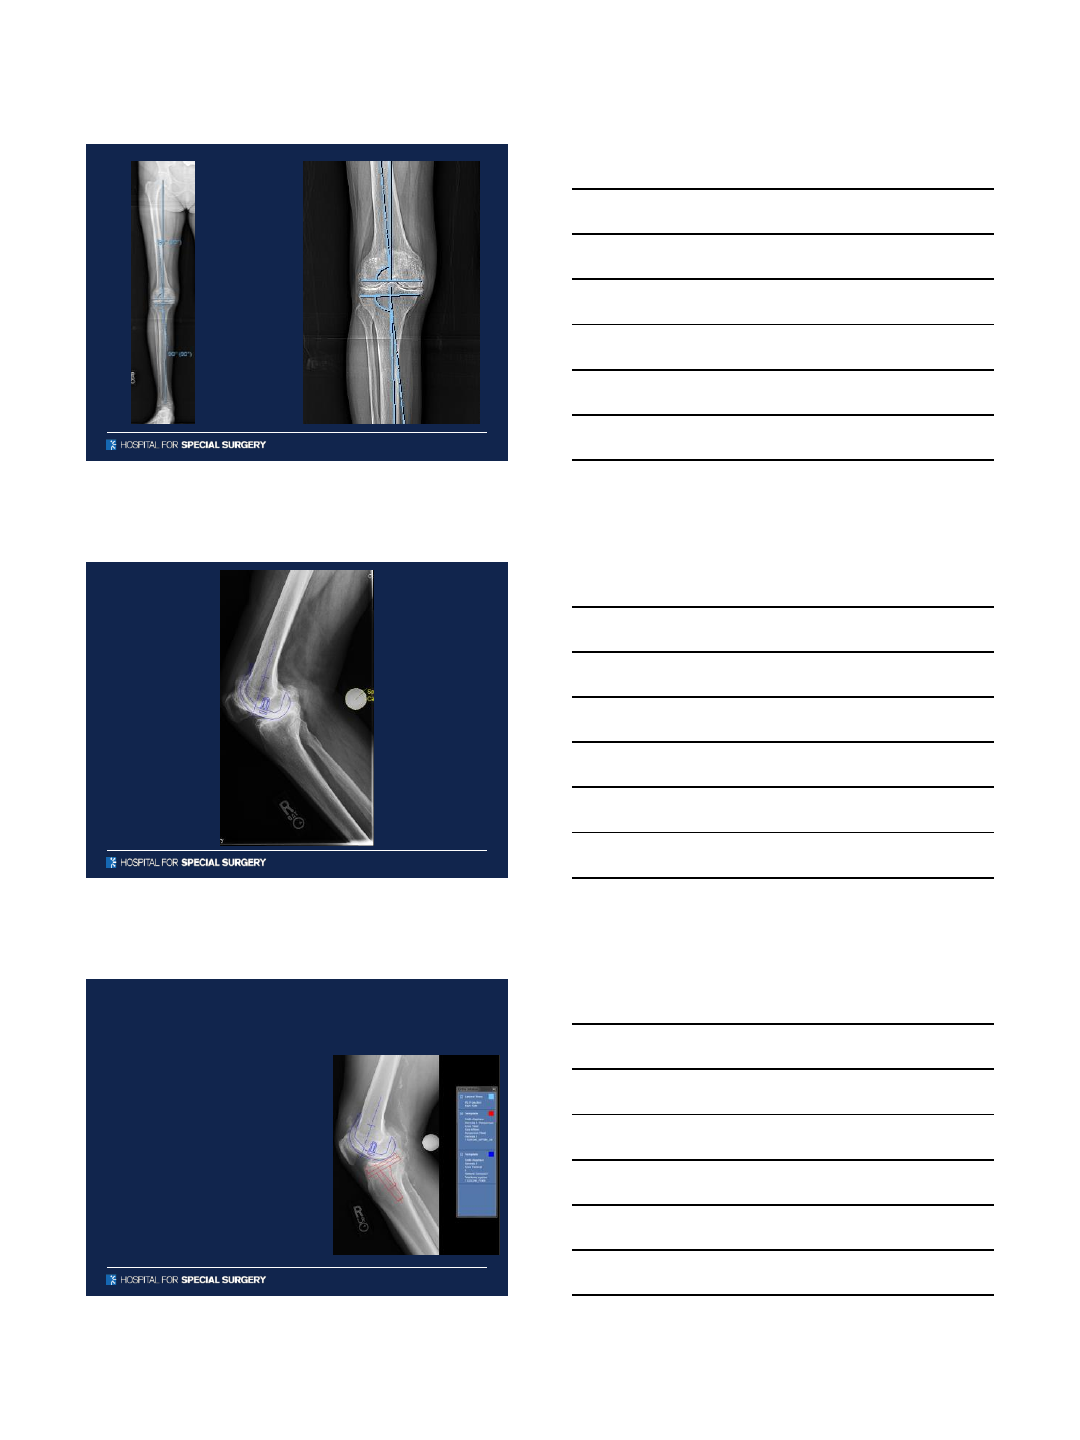

Pre-Operative Templating

Digital Templating

•Anticipate sizes of components

•Avoid leg length discrepancy

•Restore offset

•Avoid femoral fracture

•Avoid instability

Accuracy of Digital Templating for

TKA

•N=71 patients (76 knees)

•Standing anteroposterior and

lateral knee digital

radiographs

•Calibrated using a 25mm

calibration marker

•Templated sizes for the

femoral and tibial

components compared to

implanted sizes.

Results

Tibia and Femur were both exact = 43/76 (63%)

Tibia and Femur ±1 size = 74/76 ( 97%)